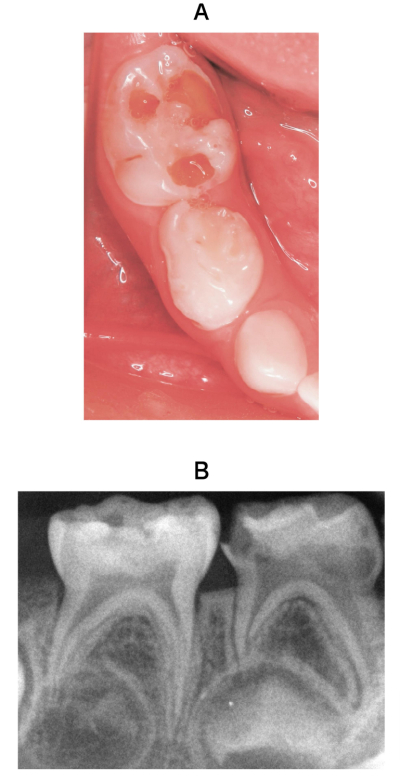

3歳の男児。下顎右側乳臼歯部の自発痛を主訴として来院した。初診時の口腔内写真とエックス線画像を別に示す。検査結果を表に示す。

治療方針の組合せで適切なのはどれか。1つ選べ。

E⏋    D⏋